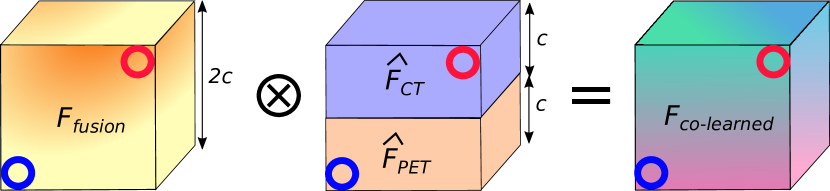

The fusion operation (depicted in Fig. 3) integrates the modality-specific feature maps according to the values (coefficients) in the multi-modality fusion map, as follows:

| (4) |

where is the fused co-learned feature map, is the stacking operation, and is an element-wise multiplication. This process merges the two modality-specific feature maps and and weights them by the co-learned multi-modality fusion map , similar to pixel intermixing. Our CNN (Fig. 1) generates four fused feature maps, one for each pair of encoder blocks. These fused feature maps are passed to the reconstruction part of the CNN (see Section II-E).